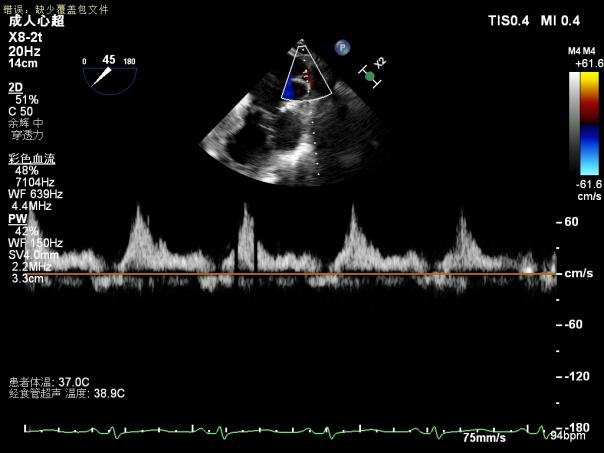

术后即刻超声提示二尖瓣反流下降至微量,二尖瓣平均跨瓣压2mmHg,多切面证实夹合组织充分,左上肺静脉多普勒波形由反向恢复正常。

2.X-plane切面调整瓣膜夹的位置:主要定位PISIA最明显的A2/P2区,分别二尖瓣交界联合切面和 LVOT切面调整夹子轴向,同时在3D切面上观察夹子方位和区域,瓣膜夹位置良好,轴向和方位均理想后,捕获A2/P2偏1区处的前后瓣叶,逐渐关闭瓣膜夹,TEE显示二尖瓣反流明显减轻至微量,3D视角显示组织桥连续完整,瓣叶抓捕稳定。彩色血流提示微量的瓣膜反流,测量平均跨瓣压差3mmHg,复查左上肺静脉血流频谱恢复正向,手术效果理想,逐步释放瓣膜夹系统撤出体外。